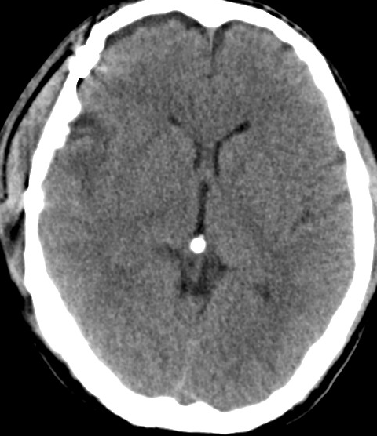

2014-9-29 CT

2014-10-5 CT